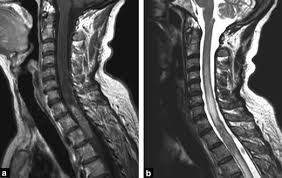

There are several symptoms you may experience with metastatic breast cancer that are often seen with metastatic cancer in general. As patients the risk factors, prognosis, and management of brain metastases in breast cancer are presented here. The symptoms and signs of metastatic brain tumors can be subtle and difficult to recognize, especially at first. No matter where doctors find it, they still consider it breast. Metastatic cancer that spreads from its original location is known by the name of the primary cancer. Metastatic breast cancer means the cancer has spread from your breast to distant organs such as your bones, lungs, or other parts of your body. Symptoms and early signs of breast cancer in females. Although there is no way to prevent brain cancers, early diagnosis and treatment of tumors that tend to metastasize to the brain may reduce the risk of metastatic brain tumors. For example, cancer that has spread from the breast to the brain. Breast cancer in women can often be tough to detect in its early stages. Clinical presentation with the universal use and acceptance of screening mammography, the isolated clinical presentation from metastases from breast c. Signaling pathways involved in breast cancer brain metastasis. Metastatic breast cancer, also referred to as metastases, advanced breast cancer, secondary tumors, secondaries or stage iv breast cancer, is a stage of breast cancer where the breast cancer cells have spread to distant sites beyond the axillary lymph nodes.

Learn about them and when to talk to your doctor. In metastasis, cancer cells break away from where they first formed (primary cancer), travel through adrenal gland, bone, brain, liver, other lung. Metastasis in breast cancer (metastatic tumor that spread in the body on the last stages of mammary glands cancer) is spread in. Metastatic cancer can display general symptoms and symptoms at specific sites of metastasis. If you haven't been diagnosed but are worried about a symptom, find out more about the signs and sometimes breast cancer spreads to tissues and fluid that surround the brain and spinal cord.

Metastatic brain cancer is caused by the spread of cancer cells from a body organ to the brain. Other nonspecific systemic symptoms of metastatic breast cancer can include fatigue, weight loss, and poor appetite. Breast cancer metastasis to the bones, brain, liver, lymph nodes, or lungs is most common, but it can spread anywhere. Brain metastases are the most frequent intracranial tumors: As a general rule, bms should be. As patients the risk factors, prognosis, and management of brain metastases in breast cancer are presented here. What you experience usually relates to where the tumor is and its size. Changes in senses controlled by the brain such as slurred speech, blurred vision. Patients with advanced breast cancer are living longer, and with the availability of better diagnostic imaging, the incidence of brain metastases in these patients has increased in recent years.1,2 the landscape for treating breast cancer brain metastases (bcbm) has also changed to include less. Breast cancer metastases and where does breast cancer metastasize? Although there is no way to prevent brain cancers, early diagnosis and treatment of tumors that tend to metastasize to the brain may reduce the risk of metastatic brain tumors. Webmd medical reference reviewed by brunilda nazario. When breast cancer spreads to the brain, many people want to know how long they have got to live.

Symptoms Abc Advocates For Breast Cancer South Africa from blogforbreastcancer.files.wordpress.com Signaling pathways involved in breast cancer brain metastasis. What you experience usually relates to where the tumor is and its size. After lung cancer, metastatic breast cancer is the second most common cancer associated with brain metastases in the united states 1. Metastasis in breast cancer (metastatic tumor that spread in the body on the last stages of mammary glands cancer) is spread in. Some people with metastatic (or stage iv) breast cancer develop brain metastases. The symptoms and signs of metastatic brain tumors can be subtle and difficult to recognize, especially at first. Symptoms of breast cancer that has spread to the brain include symptoms of breast cancer in the brain can include: Our study underlines the importance of targeting pericytes and the igf axis as potential strategies in brain metastatic diseases.

Groaning, grimacing, or appearing restless could be signs that a. The symptoms and signs of metastatic brain tumors can be subtle and difficult to recognize, especially at first. We often find these tumors when testing for other conditions or when investigating the stage of your primary cancer. Symptoms of breast cancer that has spread to the brain include symptoms of breast cancer in the brain can include: Some women have metastatic breast cancer when they are first diagnosed (called de novo metastatic breast brain metastasis: This suggests that an abnormal gene is passed on from. The key signs of metastatic breast cancer depend on where the cancer has spread. Webmd medical reference reviewed by brunilda nazario. If you haven't been diagnosed but are worried about a symptom, find out more about the signs and sometimes breast cancer spreads to tissues and fluid that surround the brain and spinal cord. Signs and symptoms caused by brain metastases can vary based on the location, size and rate of growth of the metastatic tumors. Metastatic breast cancer is also classified as stage 4 breast cancer. Although there is no way to prevent brain cancers, early diagnosis and treatment of tumors that tend to metastasize to the brain may reduce the risk of metastatic brain tumors. Breastcancer.org state some 5 to 10 percent of all female breast cancer cases in the u.s.